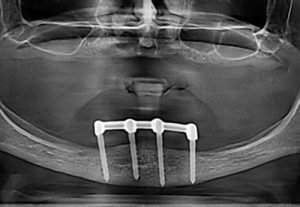

– „all on four“ „all on six“ – methodology for implant treatment teethless maxilla and mandible

Prosthetic treatment in a toothless jawbone carried - 4 implants